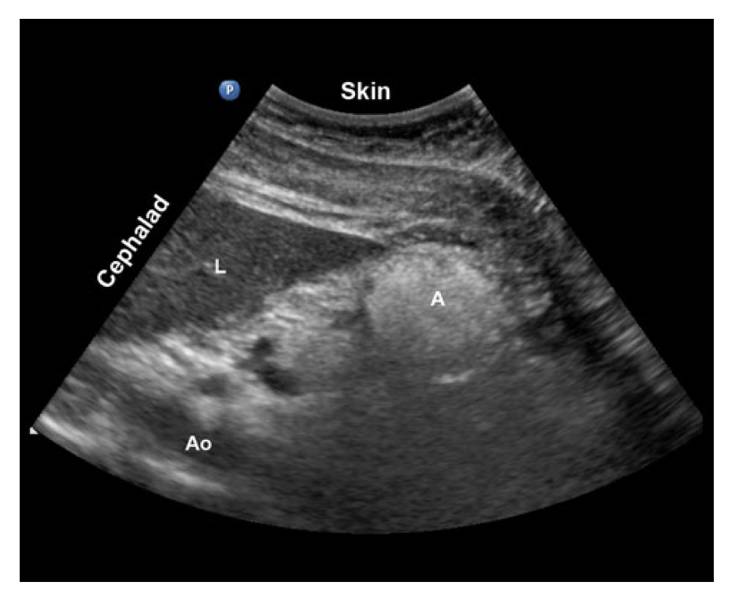

?影像定位:肝左叶、肠系膜上动脉和腹主动脉作为解剖标志

检查平面【1】

胃窦CSA(cross-sectional area) A: 根据测量的胃窦前后径(AP)和头骶径(CC)计算CSA:CSA=(AP×CC×π)/4 B:“自由示踪”法计算CSA